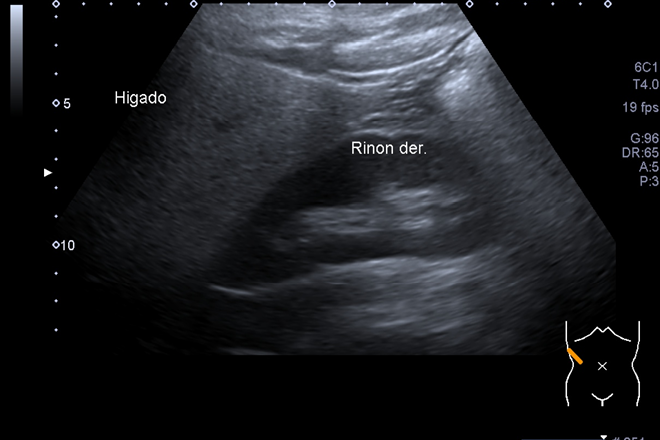

Ecografía hepática

Ecografía hepática El hígado es el órgano más grande del cuerpo humano, con un peso de aproximadamente 1500 gramos en adultos. Entre sus funciones se encuentra la contribución al mantenimiento de la homeostasis metabólica y al proceso de depuración de toxinas, además de recibir el retorno venoso del tracto gastrointestinal